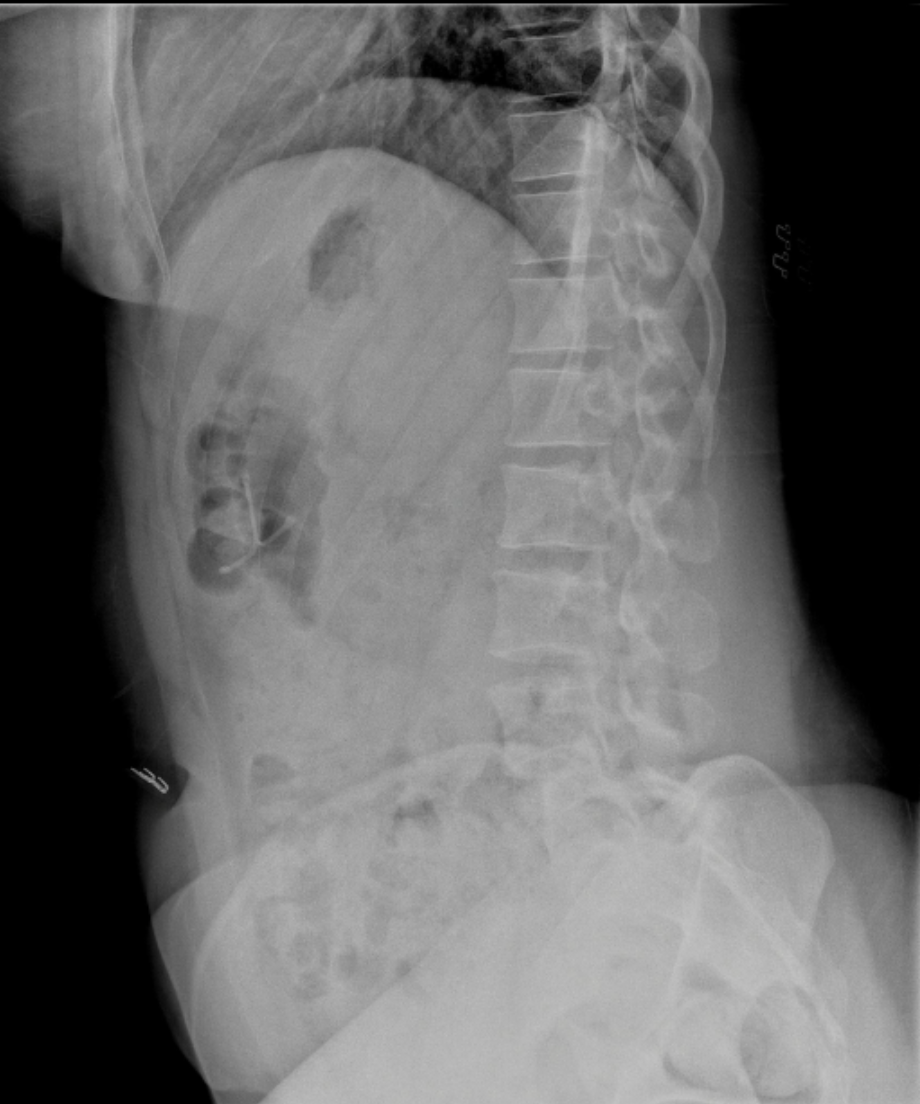

Raio_X_DIU

Radiografia de abdome (perfil). Observa-se dispositivo intrauterino (DIU) projetado fora da topografia uterina, localizado na cavidade abdominal, compatível com perfuração uterina e migração do dispositivo. Achado raro, porém relevante, com potencial risco de complicações.